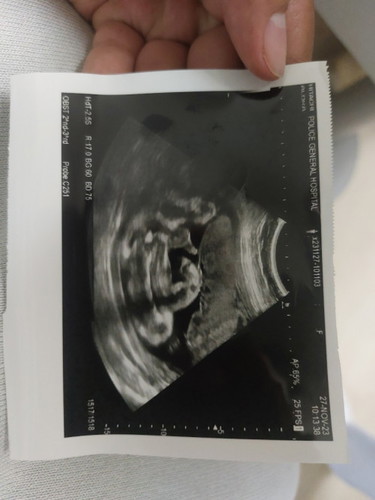

แม่ๆช่วยดูหน่อยค่ะหญิงหรือชาย

ซาวตอน30วีค

ผู้ชายหรือเปล่าคะ เราก็ดูไม่ค่อยเป็น. แต่เหมือนเห็นเป็นกะจู๋